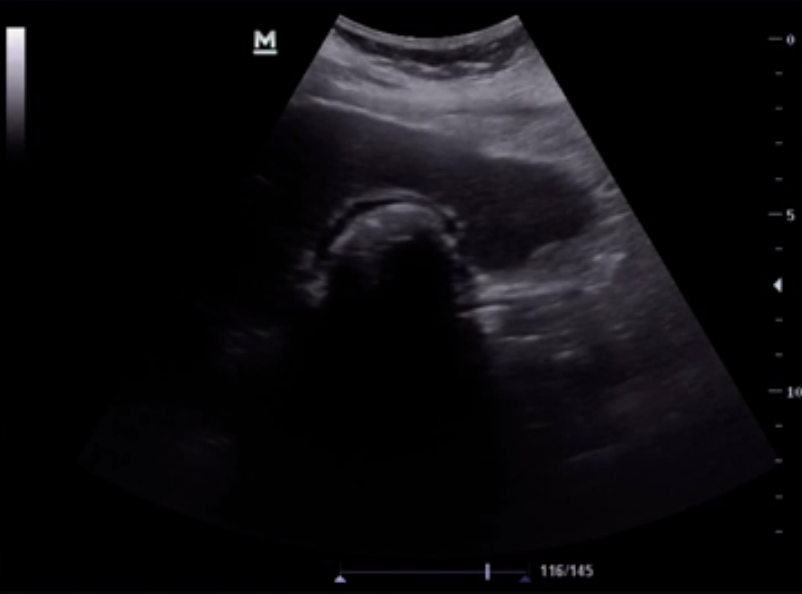

• If you are having difficulty finding the gallbladder and only see a large hyperechoic line with posterior shadowing, this may actually represent a gallbladder that is completely full of gallstones. This is known as the 'wall echo shadow' sign (seen above). So before you say you can't find the gallbladder be sure you aren't missing this finding.

• Gallstones in the gallbladder neck can sometimes be hard to identify as bowel gas shadowing often blends in with the shadowing from the gallstone. Having the patient roll to left or the right can assist with visualization of the stone as it moves via gravity.